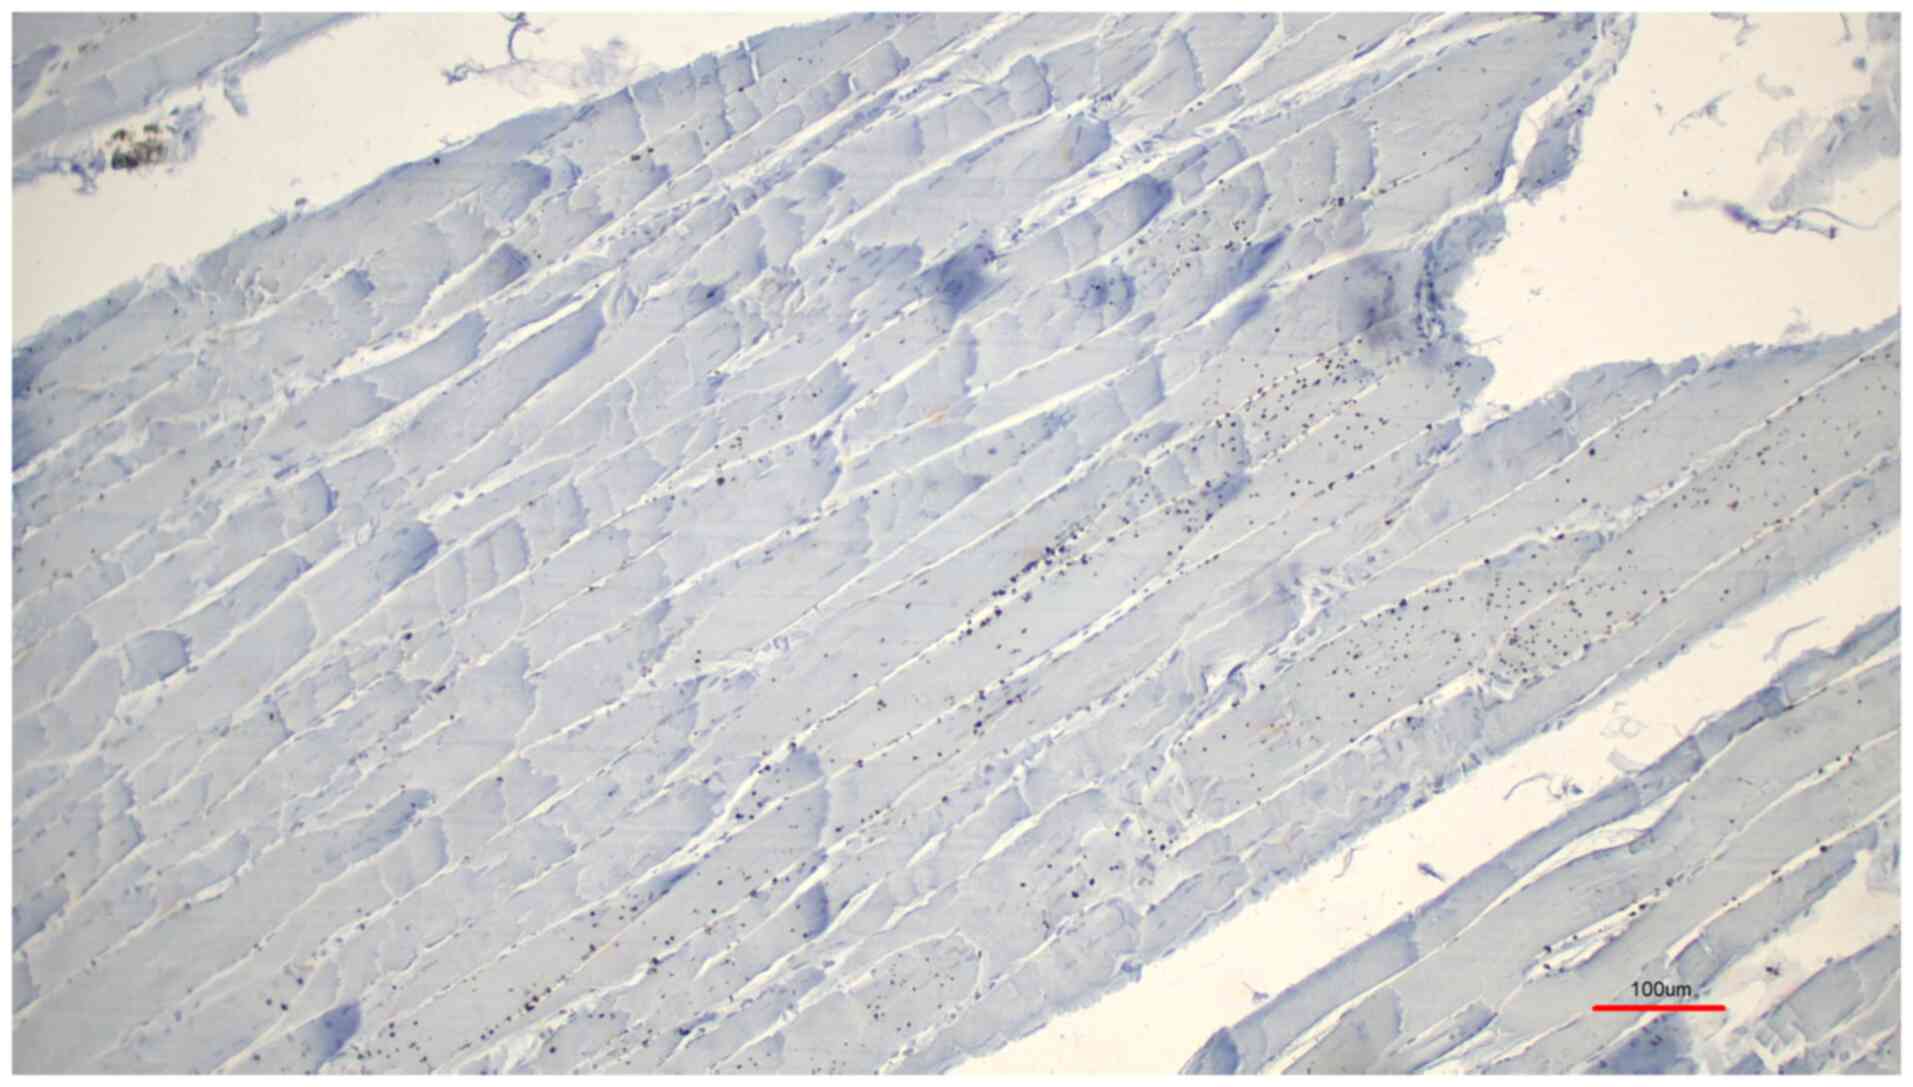

The results were evaluated microscopically and the samples were categorized according to staining intensity: Strong, weak and negative. From all the investigated samples, 19 samples exhibited strong staining and 2 samples exhibited weak staining. Nearly all (11 out of 12) samples that were preserved according to a protocol in a previous study by Janczyk et al (11) showed a strong immunohistochemical signal (Fig. 1, M. pectoralis major), while one sample was weakly stained. The four unfixed skeletal muscle samples consistently showed a strong immunohistochemical signal similar to the protocol by Janczyk et al (11). The five samples preserved using classical formaldehyde fixation showed a strong immunohistochemical signal in four cases (Fig. 2, M. triceps brachii), and a weak signal was detected in one case. Both controls, the normal rabbit serum control (Fig. 3) and the control with the peptide pre-incubation (Fig. 4), exhibited almost no immunohistochemically-stained structures. Another representative example of the presence of TRPC6 was revealed in a sample of M. deltoideus, which was obtained from an autopsy of a non-preserved cadaver (Table I, donor 8; Fig. 5, M. deltoideus). Collectively, representative examples of TRPC6 detection in human bodies are presented in M. deltoideus (Fig. 5), M. pectoralis major (Fig. 1) and M. triceps brachii (Fig. 2). An example of M. rectus femoris was lacking since it appeared identical to the other skeletal muscles. Skeletal muscles were presented from three different post mortem conditions: Non-preserved (Fig. 5), preserved according to the protocol by Janczyk et al (11) (Fig. 1) and preserved using classical formaldehyde fixation (Fig. 2).

Representative result of immunohistochemistry of a formaldehyde-fixed sample of Musculus triceps brachii presented as a control using serum of a non-immunized rabbit (Table I, donor 1). The skeletal muscle fibers are not labelled with color.

Figure 4

Representative result of immunohistochemistry of a formaldehyde-fixed sample of Musculus triceps brachii presented as a control using pre-incubation with the peptide (Table I, donor 1). The skeletal muscle fibers are not labelled with color.

Figure 5